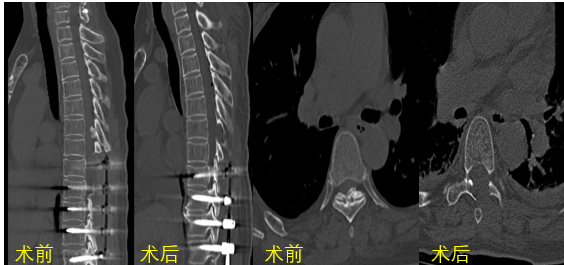

姜主任仔细查体后,确诊患者为“L1骨折,胸椎管狭窄症”。考虑到王阿姨年岁高,手术创伤性大,姜主任决定将治疗方案拆分成两个步骤,第一次手术行“胸椎椎板切除减压术+椎弓根钉内固定术+经皮椎体球囊后凸成形术”,第二次行“内镜下胸椎椎板切除减压术+黄韧带切除术”。

T8-T12椎板切除减压、L1骨水泥强化

胸椎管狭窄黄韧带骨化症是一类高致残性疾病,薄薄的神经如同松软的豆腐,任何一点损伤都可能导致不可逆的后果,切除骨化的黄韧带就好比在刀尖上表演舞蹈。姜主任将最新的UBE技术应用到王阿姨的手术治疗中,通过3个1cm的小切口在内镜下顺利从胸椎后方对T5-T7椎板完成了切除减压,并通过薄化技术一点一点切除骨化的黄韧带,用时153分钟顺利完成了“内镜下胸椎椎板切除减压术+黄韧带切除术”,术中出血60ml。术后,患者下肢麻木症状明显好转。在医院稍作休养后,即顺利康复出院。这次的UBE微创手术让王阿姨的印象尤为深刻,切实体会到了微创手术的神奇。